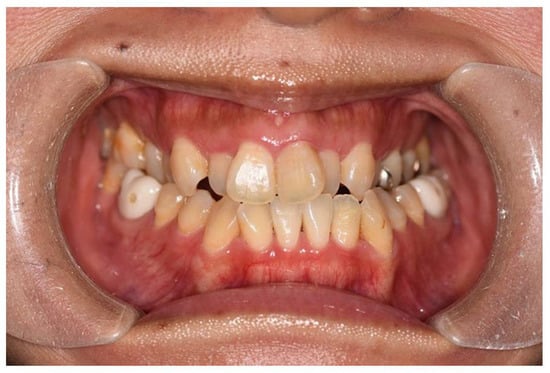

The patient was a 32-year-old female gym instructor who was referred to our plastic surgery department by an orthodontist for orthognathic surgery. She presented with Angle Class III malocclusion, an edge-to-edge bite with crowding, and maxillary arch constriction (Figure 1). An antero-posterior cephalometric analysis revealed an alveolar width discrepancy. In the study model analysis and coronal CT analysis, the distances between the functional cuspids were 37.9 mm and 47.9 mm in the maxilla and mandible, respectively. It was predicted that maxillary alveolar arch expansion through orthodontic treatment would be necessary to address the transverse arch discrepancy that would persist even after orthognathic surgery. A treatment plan was established to perform orthognathic surgery in our facility after leveraging presurgical orthodontic treatment to optimize the transverse dimension.

Angle Class III malocclusion, an edge-to-edge bite with crowding, and maxillary arch constriction were observed in the patient.

Figure 1. Initial occlusion at the first visit.